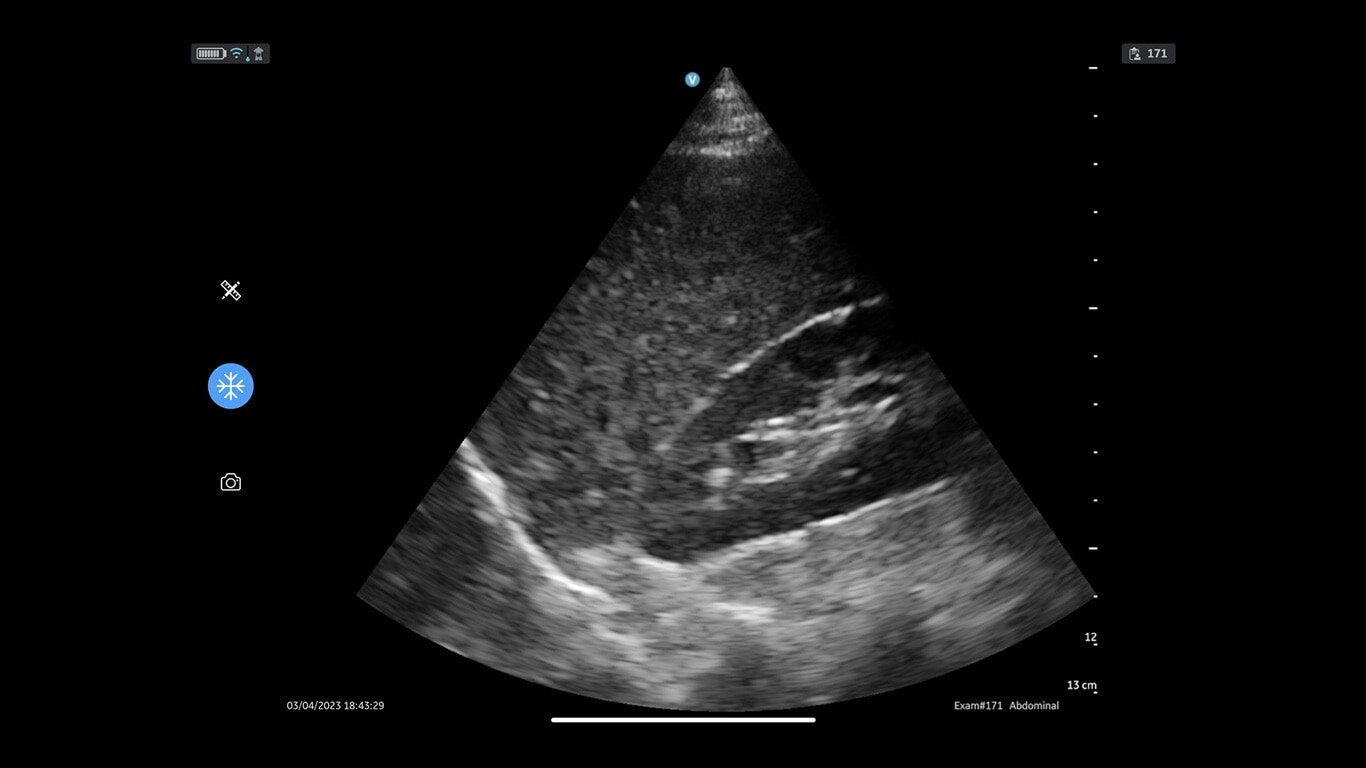

Vscan Air SL offers sector and linear transducers in a dual-probe configuration. Its sector transducer is ideal for rapid cardiac assessments. The opposite side of the probe has a linear array, so you won’t miss a beat when moving from a cardiac to a vascular assessment.

Sector array: Abdominal (Adult/Pediatrics), Urology (Adult/Pediatrics), OB/GYN, Lung/Thoracic (Adult/Pediatrics), Cardiac and hemodynamic assessment, Adult cephalic/Transcranial doppler, procedure guidance (Adult/Pediatrics).